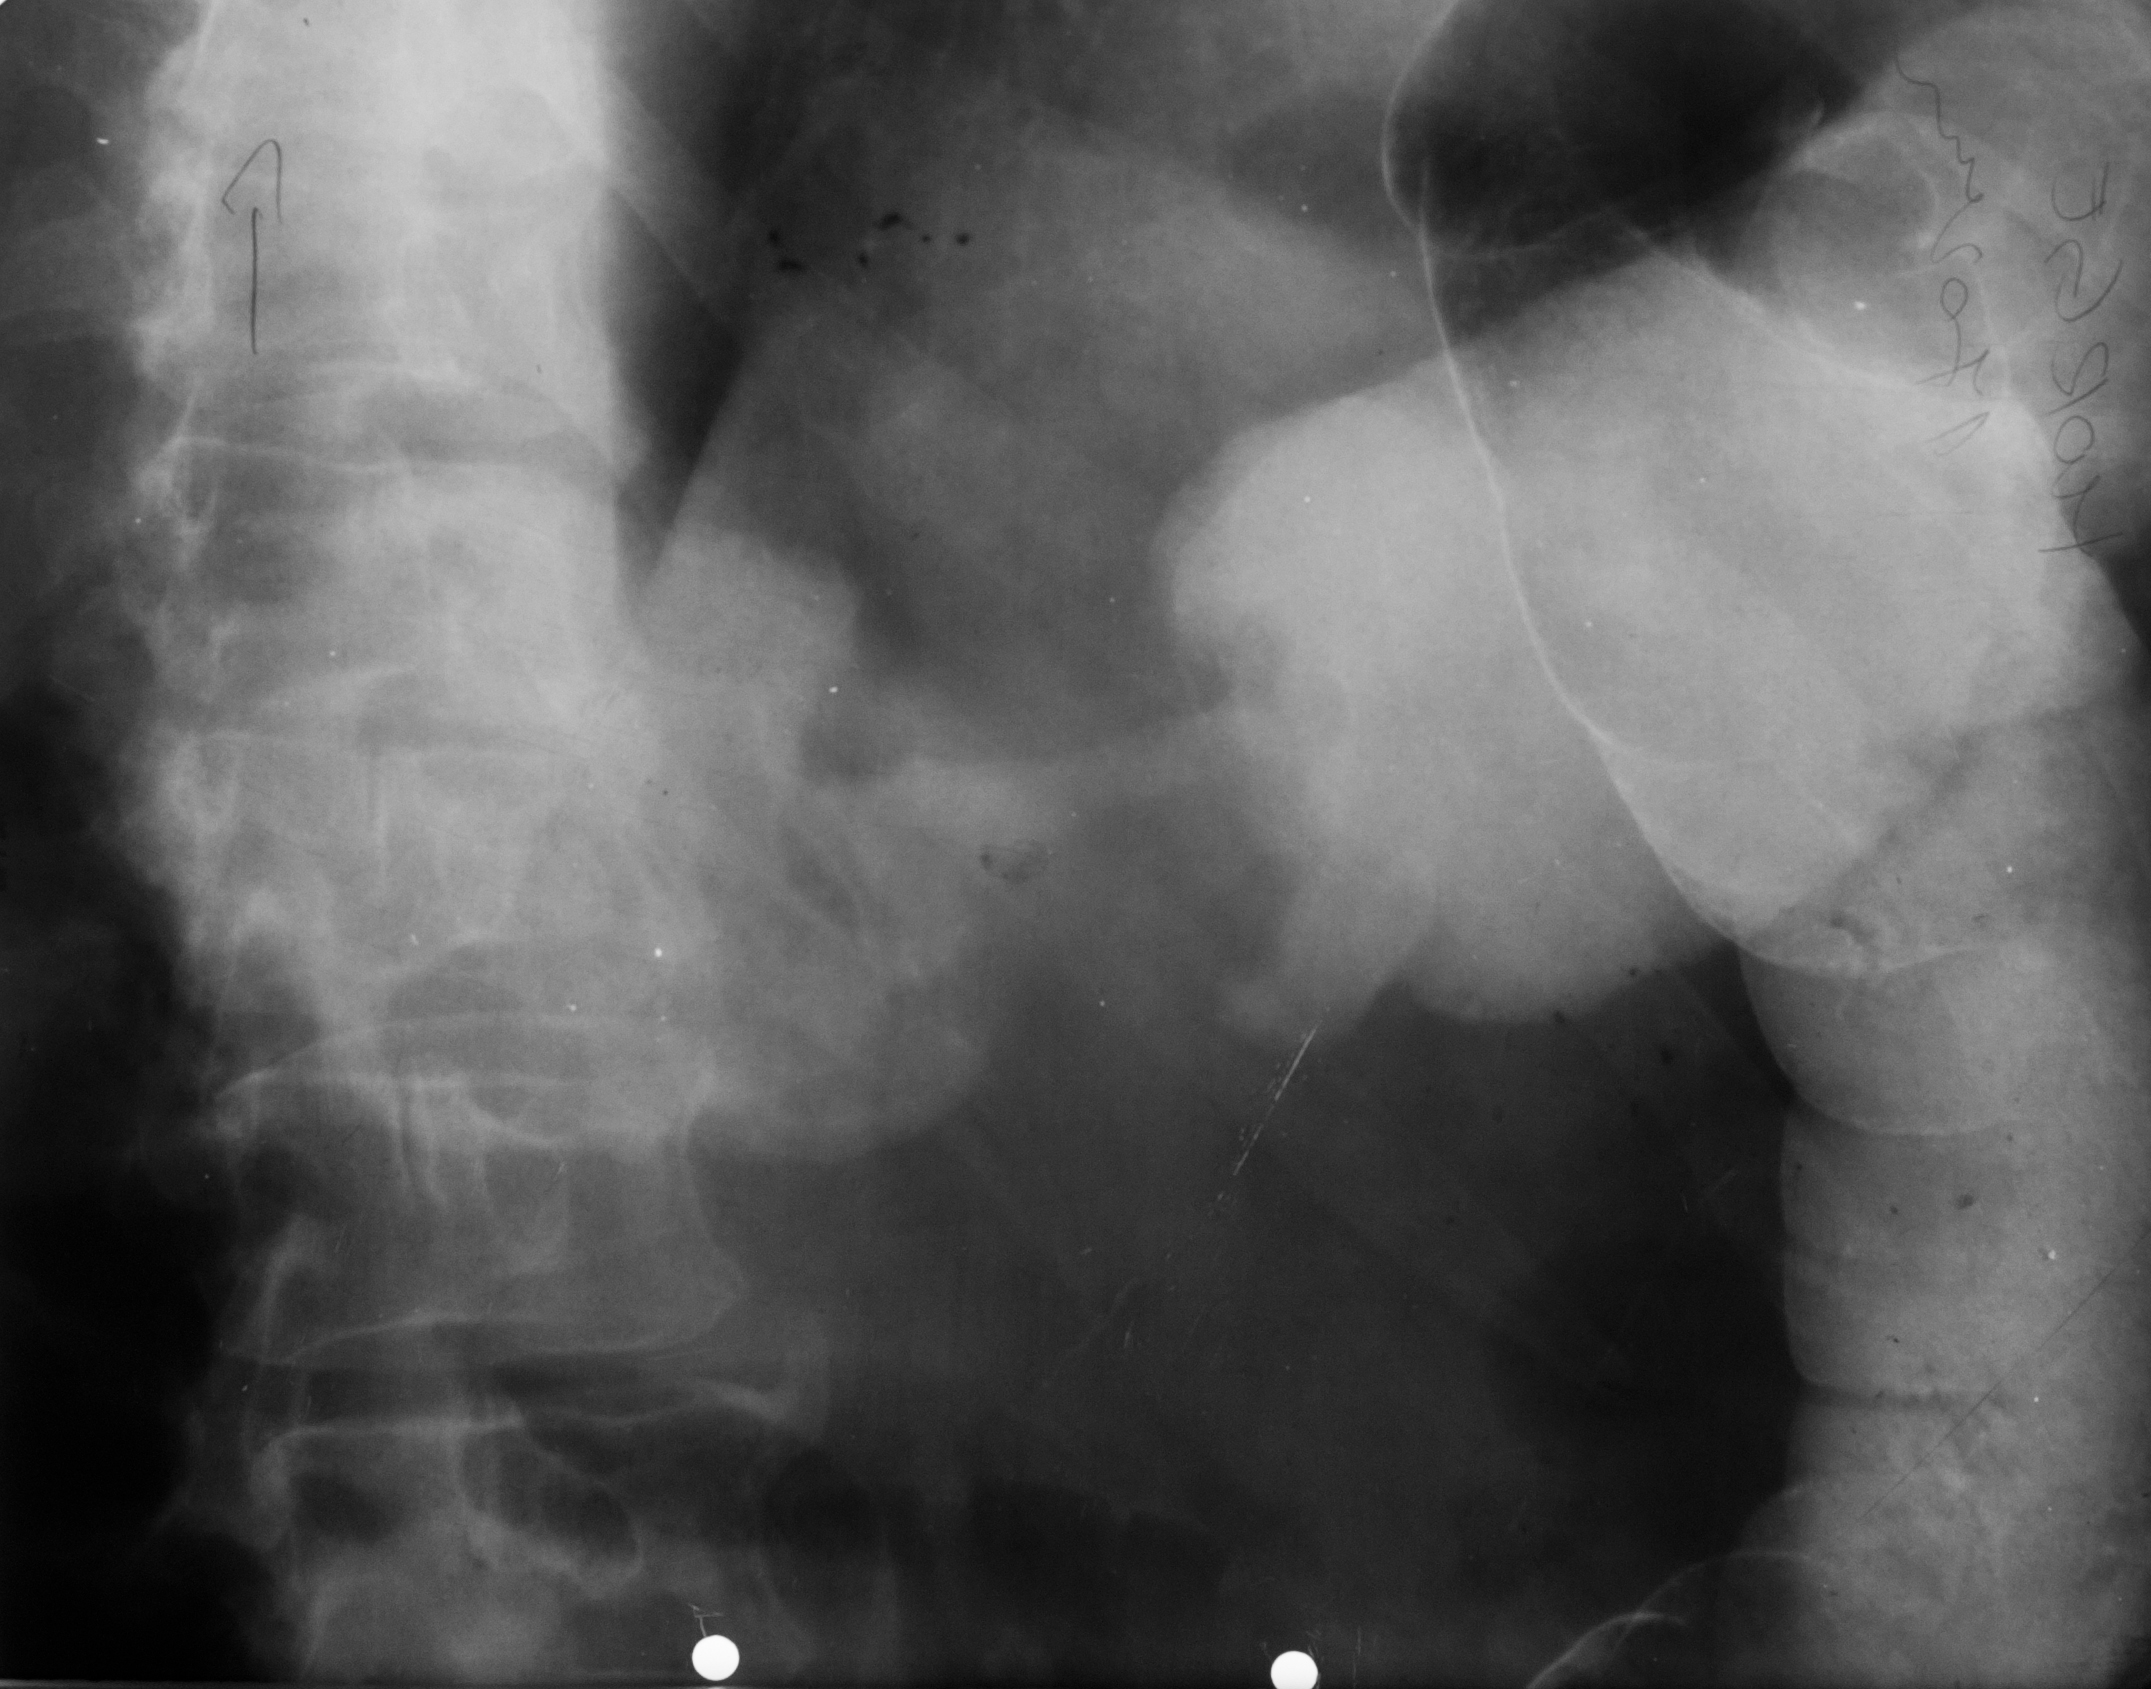

OCLUZIE LA NIVELUL INTESTINULUI SUBȚIRE

Radiografie abdominala pe gol, in etajul mijlociu, multiple imagini hidroaerice, cu ax transversal hidroaeric, cu ax transversal mai mare decat axul craniocaudal. Nivele hidroaerice de tip intestin subtire

OCLUZIE(situată mai jos) SAU ILEUS DINAMIC

Nivele hidroaerice de tip intestine gros, cu ax mare vertical si nivele hidroaerice de tip intestin subtire, posibil ocluzia este undeva mai jos sau sa fie Ileos dinamic

Imagine hidroaerica tipica de intestine gros, ax mare vertical, ax mare vertical mai mare decat ax orizontal, se vad haustrele deci clar se poate recunoaste colonul

PNEUMOPERITONEU

Imagine hipertransparenta, semilunara situate sub cupola diafragmatica dreapta